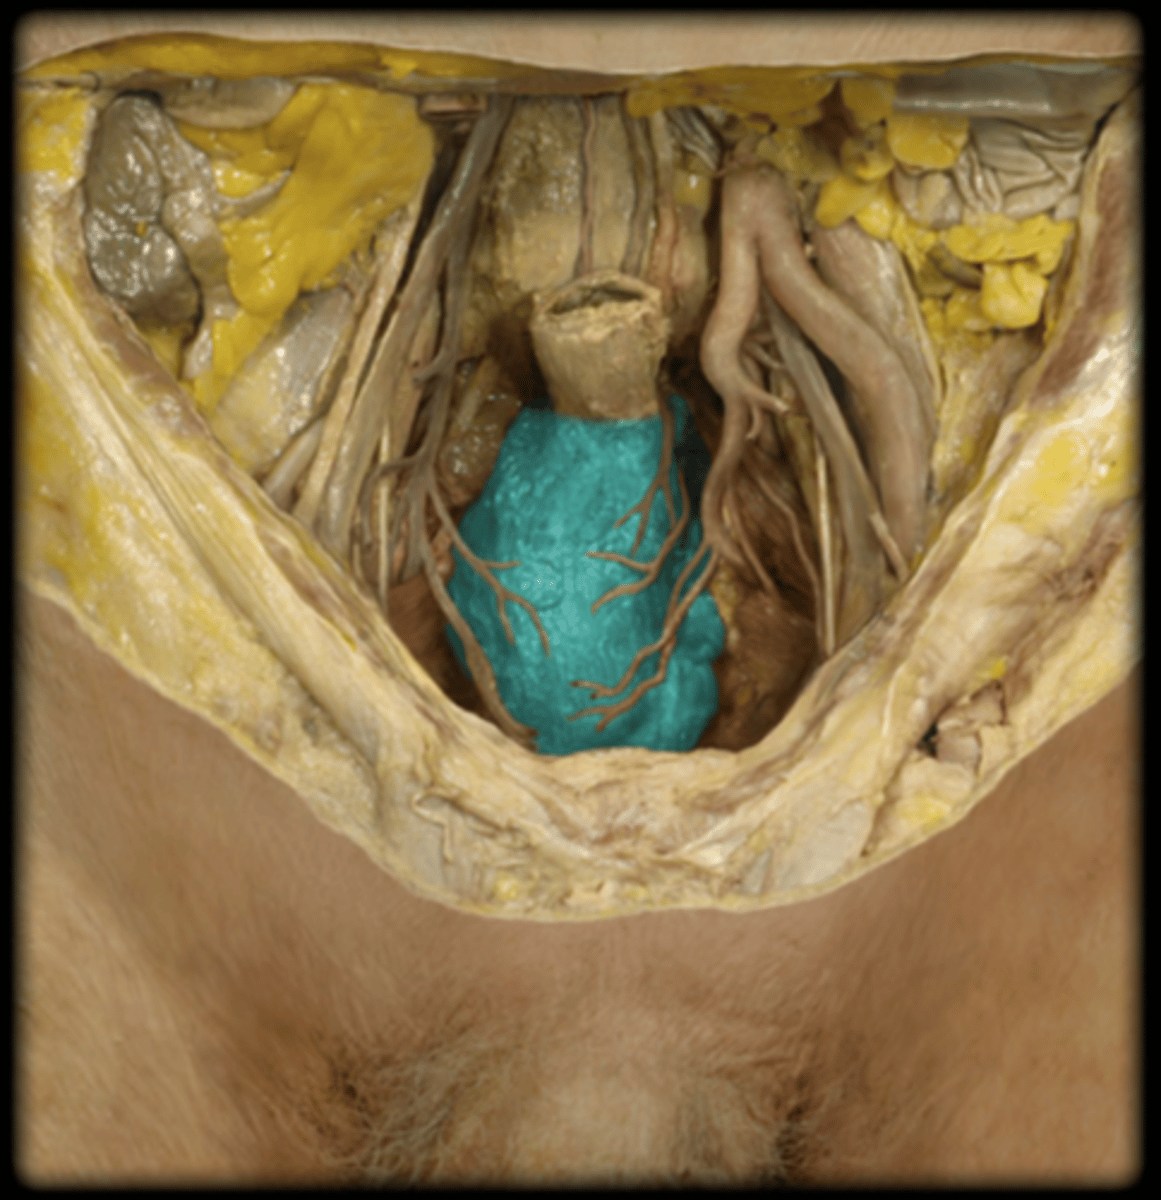

Prostate